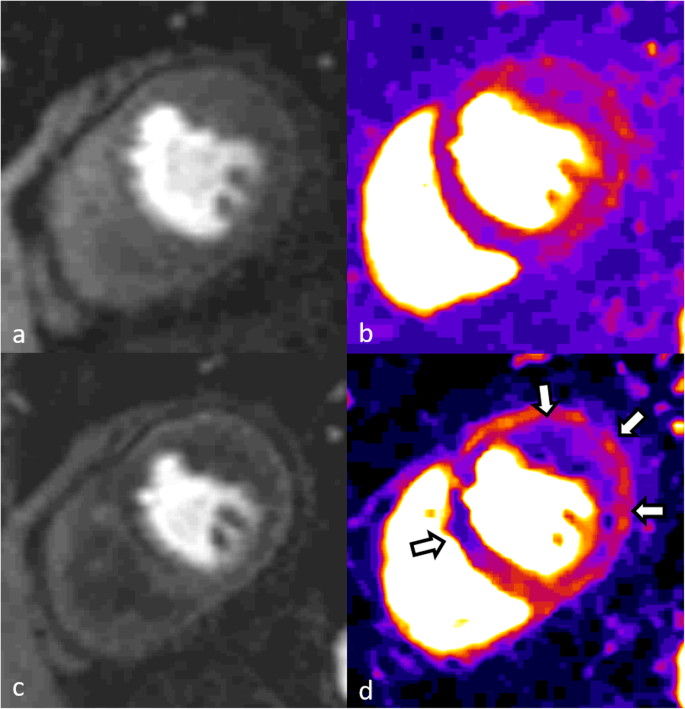

В исследовании, в котором приняли участие сотрудники из учреждений Соединенных Штатов и Канады, в течение шести месяцев использовались модели крупных животных. Было обнаружено, что при сердечных приступах, которые приводят к кровотечению в сердечной мышце, а это примерно половина всех состояний, рубцовая ткань медленно замещается жиром. По словам Дхармакумара, жировая ткань не может эффективно выталкивать кровь из сердца, и именно это приводит к сердечной недостаточности и, в конечном счете, к смерти у многих выживших после геморрагических сердечных приступов.

«Используя неинвазивную визуализацию, методы гистологии и молекулярной биологии, а также различные другие технологии, мы показали, что железо из красных кровяных телец является движущей силой этого процесса», — заключает исследователь. «Когда мы удалили железо, мы уменьшили количество жира в сердечной мышце. Это открытие открывает путь для клинических исследований по устранению или смягчению последствий, связанных с приемом железа, у пациентов с геморрагическим инфарктом миокарда».